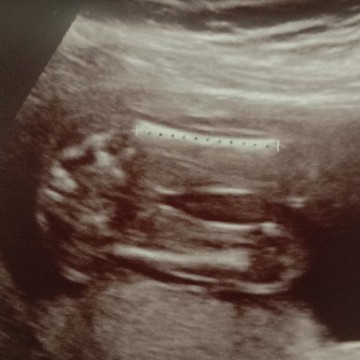

หมอบอกได้ผู้หญิงค่ะแต่แม่ไม่มันใจกล้วซื้อของไว้แล้วลูกออกมาเป้นชายเรยยากไห้แม่ๆช่วยดูหน่อยค่ะ